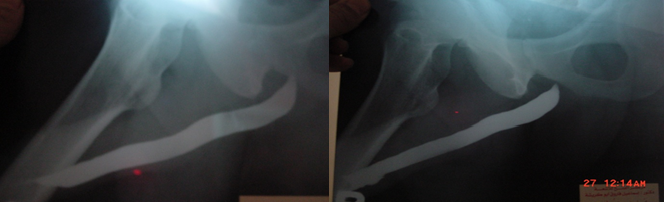

Different etiologies of the stricture of our patients were listed in supplementary Table 1. The median follow-up time was 24 months. Cosmetic assessment of all patients was carried out using Hypospadias Objective Scoring Evaluation (HOSE score) Figure S6. The postoperative surgical outcomes were listed in the Table 1. Functional evaluation was done for all cases using flow rate and ascending urethrocystogram. Mean flow rate after the repair was 15.3 ml/sec. Follow-up with urethrogram had revealed patent urethra with no stricture or diverticular formation in 39 patients Figure S7.

Figure S7 Ascending urethrocystogram showing fossa navicular stricture in image- preoperative (a) and normal postoperative normal urethral lumen in image- postoperative (b).